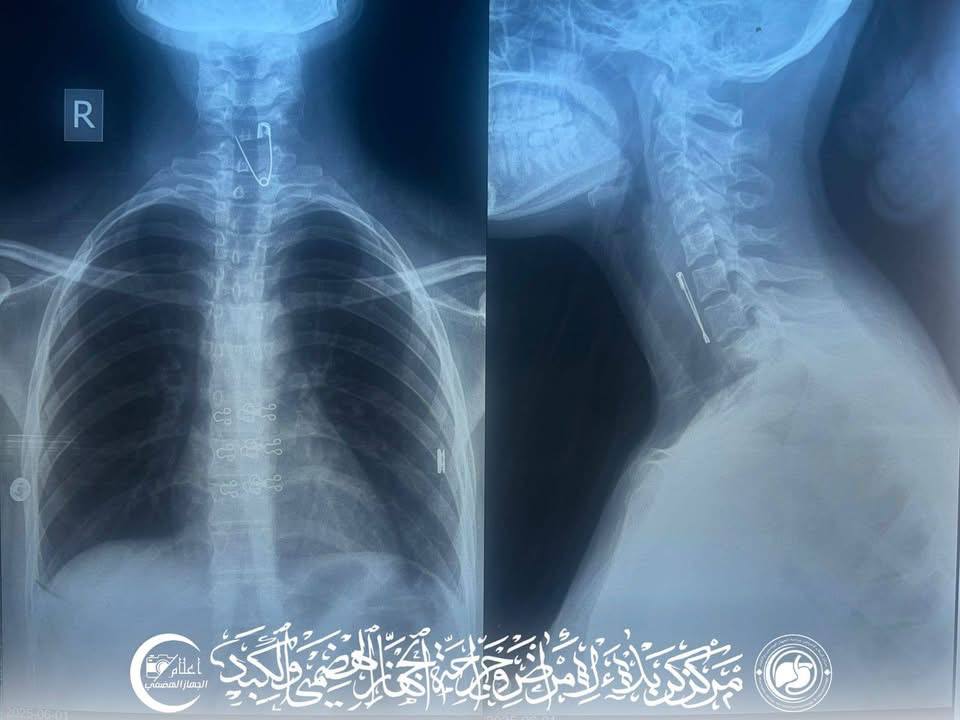

أعلنت وزارة الصحة اليوم الثلاثاء عن نجاح فريق طبي في مركز كربلاء لأمراض وجراحة الجهاز الهضمي والكبد، بإجراء تداخل منظاري طارئ لاستخراج "دبوس" من مريء فتاة تبلغ من العمر 20 عاماً.

وقالت الوزارة في بيان تلقاه كلمة الإخباري، إن "فريق طبي في مركز كربلاء لأمراض وجراحة الجهاز الهضمي والكبد، نجح بإجراء تداخل منظاري طارئ لاستخراج "دبوس" من مريء فتاة تبلغ من العمر 20 عاماً من سكنة قضاء الهندية".

وأوضح رئيس الفريق، اختصاصي جراحة الجهاز الهضمي والكبد الدكتور أكرم الجابري، أن "المريضة تم تحويلها من قسم الطوارئ في المدينة الطبية بوقت متأخر من ليلة أمس"، مبيناً أنه "تمكّنا من إزالة الدبوس باستخدام ناظور المعدة خلال 12 دقيقة فقط، وبشكل آمن دون تسجيل أية مضاعفات" ، وجرى التداخل بجهود الفريق الطبي والتمريضي والصحي الساند في المركز.